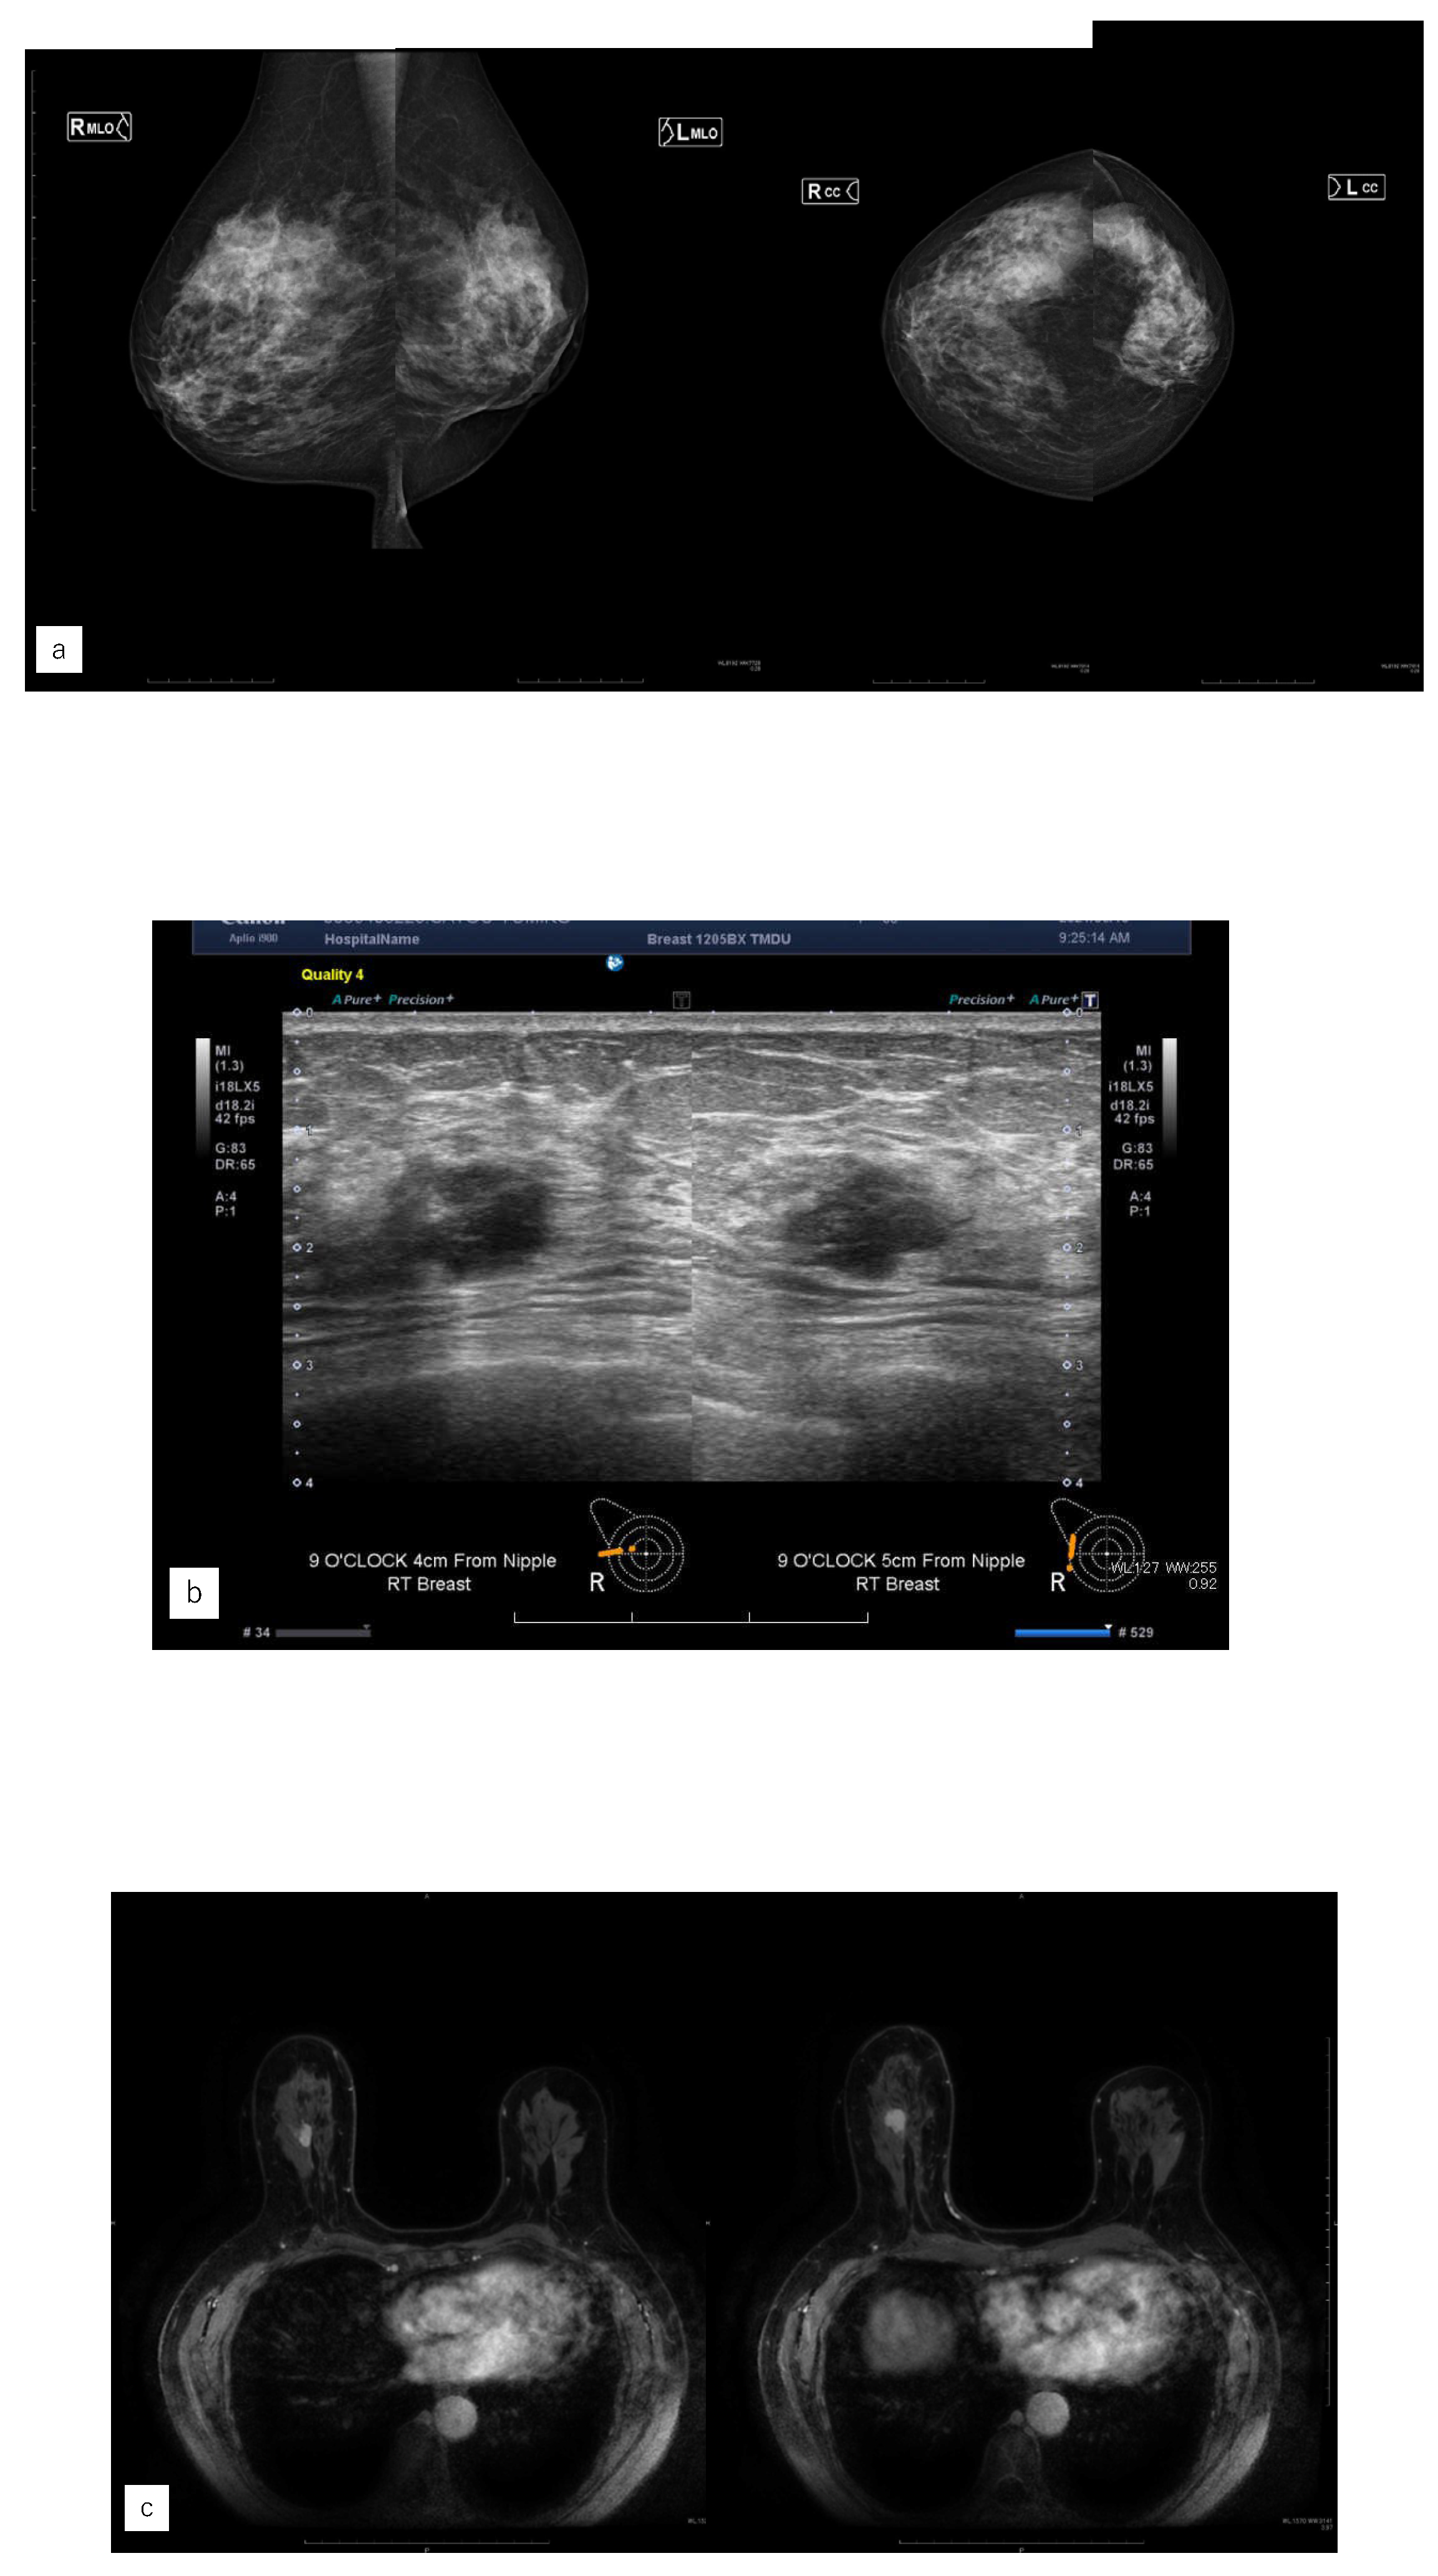

Figure 5. Representative case (case 7). (a) MG. (b) US. (c) MRI. (d) AI diagnosis.A 63 yearsold woman had left side breast cancer. Two years later, she was diagnosed with right breast cancer. It was T1c, triple negative breast cancer. (a) A mass was found in the right upper area in mammography (MG) and diagnosed as breast imaging reporting and data system (BI-RADS) Category 4. (b) Ultrasonography revealed a hypoechoic masse in the right upper outer area.(c) Magnetic Resonance Imaging revealed a mass with contrast enhancement in the left upper outer area.(d) The Artificial Intelligence system diagnosed no malignancy. The mass visible on MG was not seen on MG a year earlier. Although the mass was of the same density as the background mammary gland, the radiologists diagnosed it to be possibly malignant upon comparison and reading.